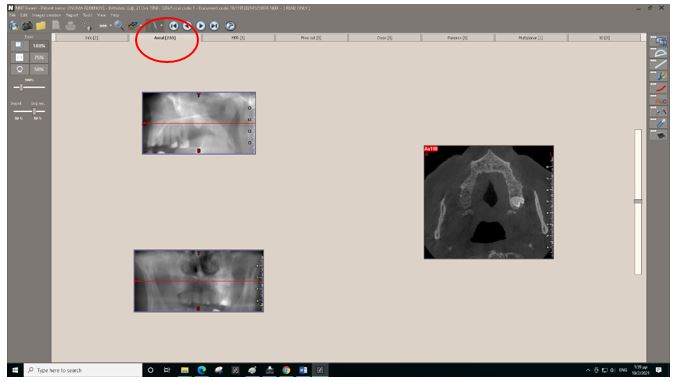

Η αρχική εικόνα του Viewer εμφανίζει τις πληροφορίες της εξέτασης.

Επιλέγοντας το Axial από την οριζόντια μπάρα μπορώ μετακινώντας την κάθετη μπάρα να δω το σύνολο των εγκάρσιων τομών.